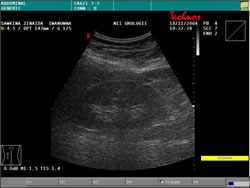

УЗИ: |

|